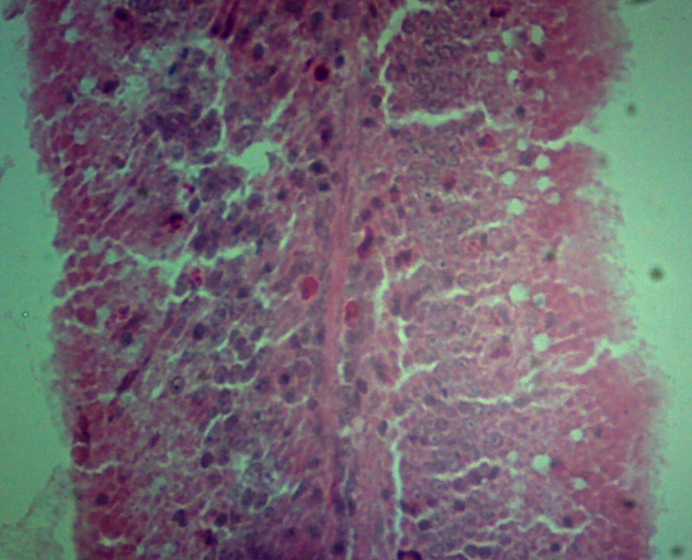

求助 肠道绒毛上的空泡是什么?脂肪变性么? 已有1人参与